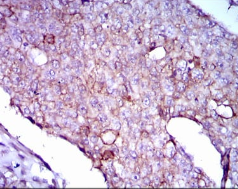

Immunogen:    Purified recombinant fragment of human LPA (AA: 1823-2013) expressed in E. Coli.

IHC    1/200 - 1/1000